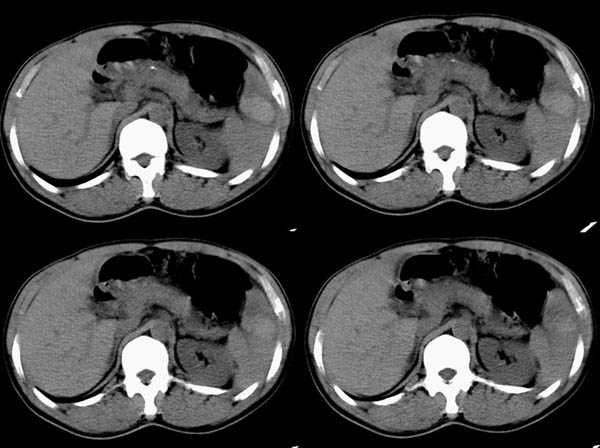

m50y以腹疼、腹胀2小时就诊。腹透肠胀气较明显,余无明显异常。做ct时腹疼已明显缓解;病人否认外伤史,否认血液病变、否认肝炎史。建议第二天做ct增强,病人第二天放弃了增强。脾脏区较高密度影ct值为60hu,正常脾脏ct值为45hu(窗宽:150,窗位:56)。

ct表现:脾脏内见较高密度影ct值为60hu,正常脾脏ct值为45hu(窗宽:150,窗位:56)。 边界清晰,周围见略低密度影

脾脏实质内高密度病变,ct值为60hu,边界清晰,无明显外伤病史,腹痛、腹胀2小时就诊,首先考虑脾脏血管瘤破裂出血。